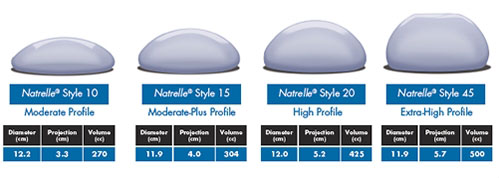

The Amazing History Of Breast Implants:Breast Implants Sizes

breastimplantssizes.blogspot.com